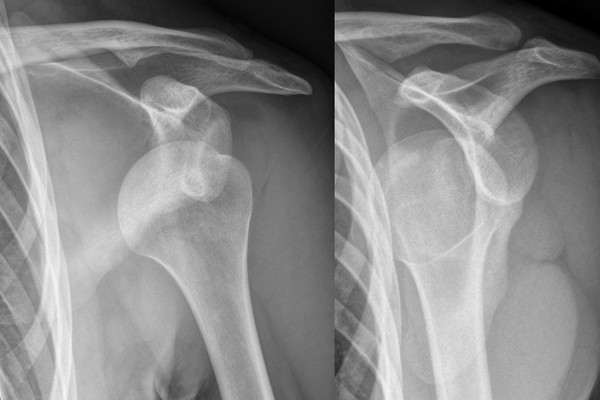

SHOULDER DISLOCATION